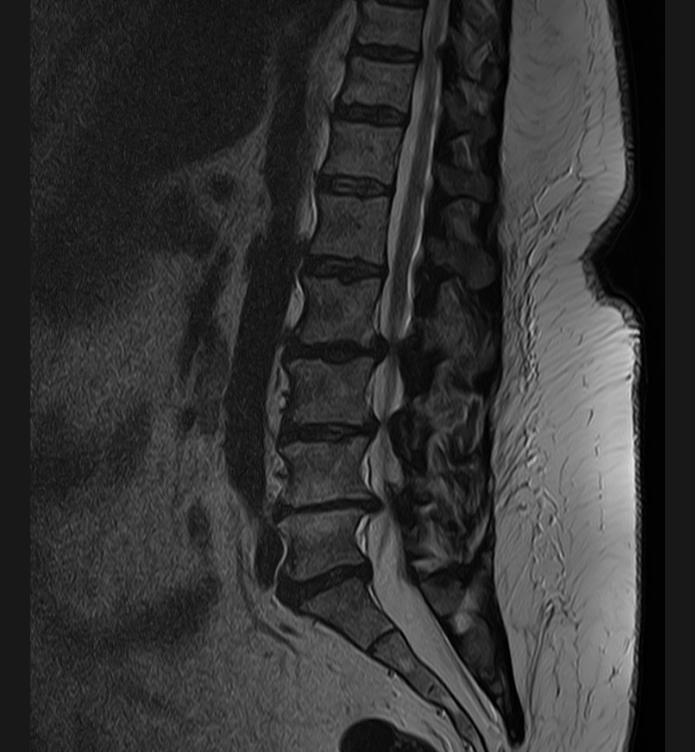

Basit Omurga ve Omurilik Anatomisi Omurga, 33 adet omur kemiğinden oluşur. Bu kemiklerin 7 tanesi boyun omuru, 12 tanesi sırt omuru, 5 tanesi bel omurudur. Beş tanesi birleşmiş olarak sakrum denilen kemiği ve 4 tanesi yine birleşmiş olarak koksiks denilen kuyruk sokumu kemiğini oluşturur. Omurganın görevi omuriliği korumak ve gövdeyi dik pozisyonda tutmak için destek […]